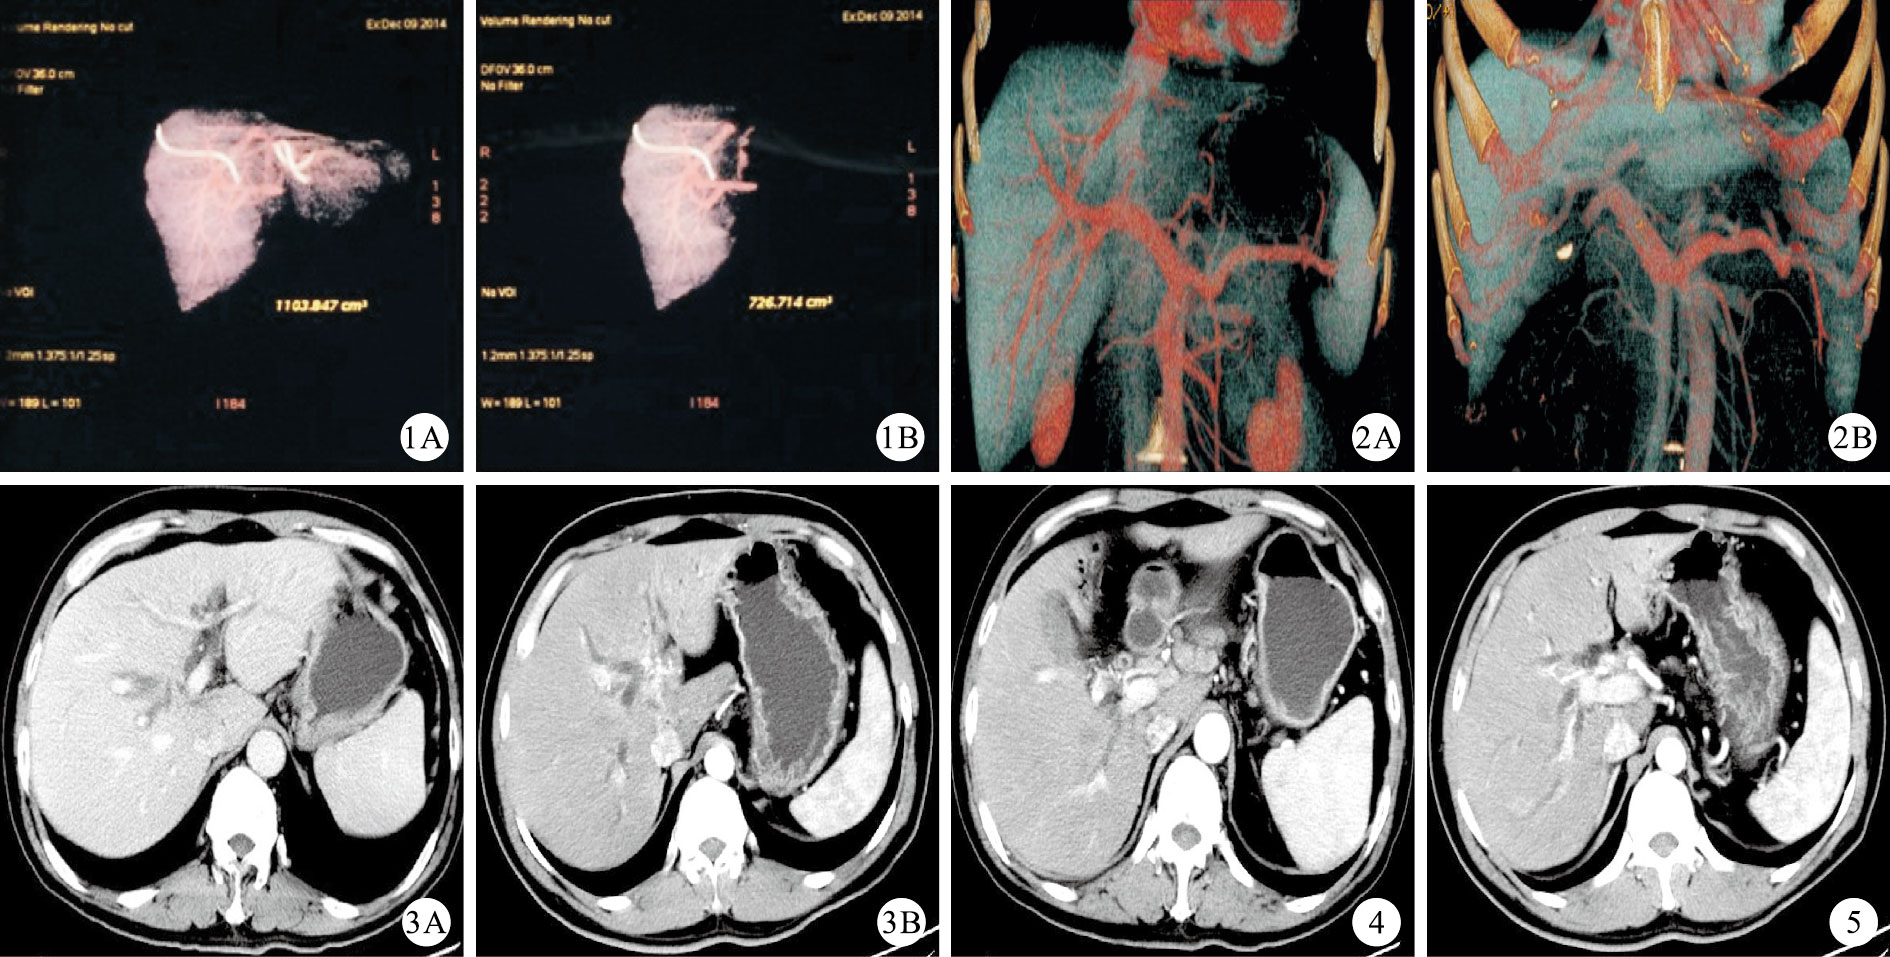

應用對比劑的增強CT和MRCP,配合新開發的各種軟件,可以獲得與ERCP成像沒有區別甚至是信息量更多的影像資料。高分辨率的動態掃描、膽管和血管成像及三維成像技術,可以使醫生較容易地了解腫瘤侵犯膽管的長度(Bismuth分型)、腫瘤近端膽管重建的條件及肝實質的侵犯情況;以及血管(包括門靜脈、肝動脈和中肝靜脈)有無侵犯、侵犯的程度、是否需要重建和能否重建;還可以大致評估淋巴結和遠處轉移的情況。根據上述資料,計劃手術切除的范圍,同時應用肝體積測量軟件測定預留肝臟的體積(圖 1)。如果估計預留的肝體積不足夠大,可以行門靜脈栓塞術,使得預留側肝體積增大,2周以后再進行肝體積測定,達到要求后再進行切除手術。

主要涉及肝臟浸潤和轉移情況以及周圍血管侵犯情況。有周圍血管侵犯的患者TNM分期在T3以上,雖然部分患者可以通過聯合血管切除改善預后,但是手術切除的風險增大且絕大多數患者的預后較差,5年生存率低,是否切除還需結合患者經濟狀況、心理預期、術后風險的承受能力等諸多人文因素考慮,若預留側肝內有轉移則是根治性切除的禁忌證。對于門靜脈、肝動脈及肝中靜脈和第二肝門的侵犯者是否切除需結合具體情況進行處理。① 門靜脈侵犯。門靜脈侵犯的情況可通過動態增強CT和血管成像來判斷(圖 2、3)。

肝門部膽管癌的門靜脈侵犯不是手術切除的禁忌證,經過選擇的患者可以安全地進行肝切除。門靜脈切除不增加手術并發癥發生率和死亡率,死亡率大約為10% [4]。至于門靜脈侵犯到什么程度才難以重建而成為手術禁忌證,則需要結合術者自身的血管外科技術,不能一概而論。一般認為,肝臟切除時預留側的門靜脈干侵犯、或從門靜脈主干近端到左右分叉部被腫瘤包繞、或門靜脈閉塞,或雙側門靜脈支均被腫瘤包繞是肝門部膽管癌手術切除的禁忌證。② 肝動脈侵犯。由于肝動脈的壁厚,壓力和彈性大,肝動脈的侵犯很難表現出像門靜脈那樣在血管成像上的血管閉塞表現,一般表現為動脈管腔變細,動脈走行移位、僵硬等。肝動脈的腫瘤侵犯時常需要在動態增強CT的動脈期水平圖像上仔細動態觀察動脈走行與腫瘤的關系才能發現(圖 4、5)。特別需要注意的是,肝動脈侵犯Bismuth Ⅲb型和部分需要切除左肝的Ⅳ型患者,由于右肝動脈走行于腫瘤的后方,很容易被侵犯。由于肝動脈的管腔較細,動脈切除后重建的技術要求高、術后通暢率低,術后一旦保留側肝臟的動脈血供差,很容易發生肝臟缺血壞死、感染等并發癥。③ 肝中靜脈和第二肝門的侵犯。肝中靜脈的侵犯在肝門部膽管癌術前的評估中要引起重視,主要涉及Bismuth Ⅲb型侵犯肝中靜脈,右肝的靜脈回流以肝中靜脈為主;以及Bismuth Ⅲa型侵犯肝中靜脈,肝臟的左內葉靜脈回流以肝中靜脈為主的情況[5],這時通常需要行左或右三葉切除,這部分患者需要術前進行門靜脈栓塞準備,否則預留的肝臟體積可能不能夠代償,術后出現肝功能衰竭。筆者曾嘗試過行左半肝加尾葉切除時,用患者自體左肝靜脈重建肝中靜脈,術后肝右前葉回流良好。目前還未見有其他肝門部膽管癌切除肝中靜脈重建的報道。而腫瘤明顯侵犯第二肝門、累及各支肝靜脈根部時則提示不能根治性切除。